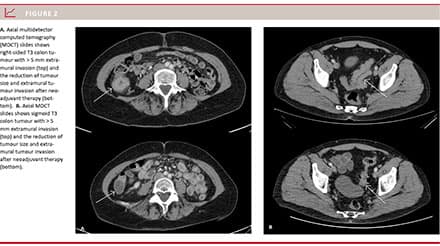

Overall, a reduction in tumour size was observed following NEC (Figure 2). The mean values for all 67 patients are shown in Table 1. The extramural tumour invasion of these advanced colonic cancers decreased from 11 mm to 6 mm after chemotherapy. The number and size of the peritumoral lymph nodes decreased. There was a statistically significant reduction in all variables after NEC compared with baseline (p < 0.001) with no overlap of the 95% confidence intervals (CIs). A tumour size reduction was measured in 90% (95% CI: 80-95%) of the 67 patients, Table 2. As to tumour size according to RECIST 1.1, 55% (95% CI: 43.3-66.5) of the patients (37 of 67) had stable disease. The two patients with tumour growth had an 8% and a 10% increase, respectively. None had progressive disease according to RECIST 1.1. 45% (95% CI: 33.5-56.7) of the patients (30 of 67) responded with a tumour size reduction of > 30%. One patient had complete response with no visible tumour after neoadjuvant chemotherapy (Table 2).

Results: The mean tumour length was 7.8 cm (95% confidence interval (CI): 5.3-10.4) at baseline and 4.34 cm (95% CI: 4.0-4.9) after treatment. The mean extramural tumour invasion was 10.6 mm (95% CI: 9.5-11.8) at baseline and 5.7 mm (95% CI: 4.7-6.7) after treatment. The mean number of enlarged lymph nodes was 4.1 (95% CI: 3.4-4.9) at baseline and 2.1 (95% CI: 1.4-2.7) after treatment. According to RECIST 1.1, 45% (95% CI: 34-57) of the patients had a response and 55% (95% CI: 43-67) had stable disease. None of the patients showed progressive disease.

Conclusion: Using CT, we demonstrated a significant reduction in tumour size, extramural tumour invasion, number and size of enlarged lymph nodes following neoadjuvant treatment.